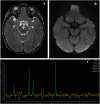

Acyl-CoA dehydrogenase 9 (ACAD9), linked to chromosome 3q21.3, is one of a family of multimeric mitochondrial flavoenzymes that catalyze the degradation of fatty acyl-CoA from the carnitine shuttle via β-oxidation (He et al. 2007). ACAD9, specifically, is implicated in the processing of palmitoyl-CoA and long-chain unsaturated substrates, but unlike other acyl-CoA dehydrogenases (ACADs), it has a significant role in mitochondrial complex I assembly (Nouws et al. 2010 & 2014). Mutations in this enzyme typically cause mitochondrial complex I deficiency, as well as a mild defect in long chain fatty acid metabolism (Haack et al. 2010, Kirby et al. 2004, Mcfarland et al. 2003, Nouws et al. 2010 & 2014). The clinical phenotype of ACAD9 deficiency and the associated mitochondrial complex I deficiency reflect this unique duality, and symptoms are variable in severity and onset. Patients classically present with cardiac dysfunction due to hypertrophic cardiomyopathy. Other common features include Leigh syndrome, macrocephaly, and liver disease (Robinson et al. 1998). We report the case of an 11-month old girl presenting with microcephaly, dystonia, and lactic acidosis, concerning for a mitochondrial disorder, but atypical for ACAD9 deficiency. Muscle biopsy showed mitochondrial proliferation, but normal mitochondrial complex I activity. The diagnosis of ACAD9 deficiency was not initially considered, due both to these findings and to her atypical presentation. Biochemical assay for ACAD9 deficiency is not clinically available. Family trio-based whole exome sequencing (WES) identified 2 compound heterozygous mutations in the ACAD9 gene. This discovery led to optimized treatment of her mitochondrial dysfunction, and supplementation with riboflavin, resulting in clinical improvement. There have been fewer than 25 reported cases of ACAD9 deficiency in the literature to date. We review these and compare them to the unique features of our patient. ACAD9 deficiency should be considered in the differential diagnosis of patients with lactic acidosis, seizures, and other symptoms of mitochondrial disease, including those with normal mitochondrial enzyme activities. This case demonstrates the utility of WES, in conjunction with biochemical testing, for the appropriate diagnosis and treatment of disorders of energy metabolism.